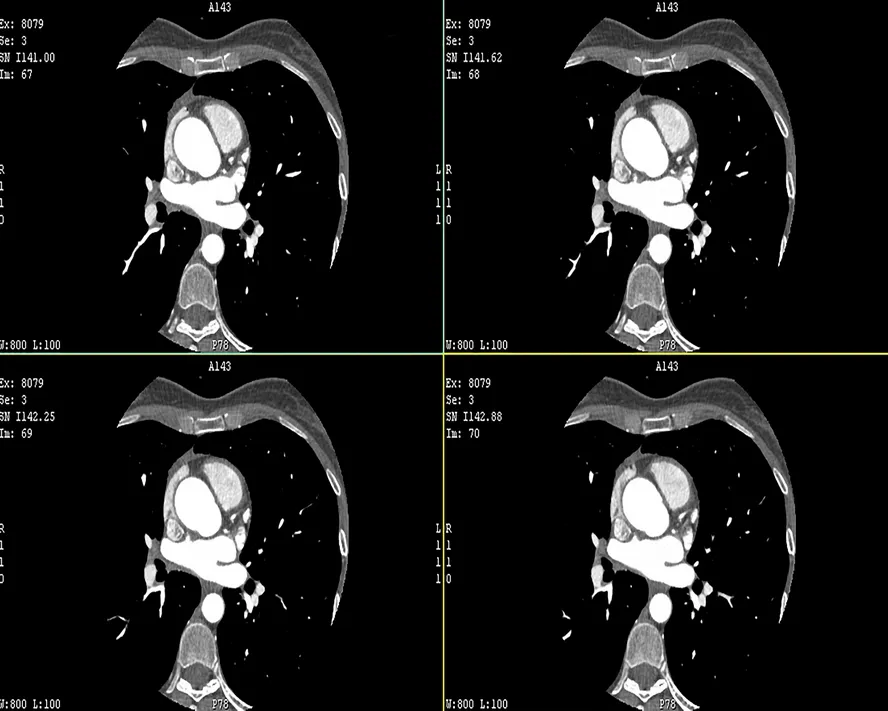

Dijital Subtraksiyon Anjiyografi (DSA), kan damarlarının detaylı görüntülenmesi için kullanılan bir tıbbi görüntüleme tekniğidir. Bu yöntem, damar hastalıklarının teşhis ve tedavisinde büyük önem taşır. DSA, yüksek çözünürlüklü görüntüler elde etmek için bilgisayar teknolojisi kullanılarak damarların iç yapısını net bir şekilde gösterir. Özellikle beyin, kalp ve periferik damar hastalıklarının tanısında yaygın olarak kullanılır.

Dijital Subtraksiyon Anjiyografi (DSA), kan damarlarını incelemek için kullanılan ileri bir radyolojik tekniktir. Geleneksel anjiyografi yöntemlerine göre daha net ve ayrıntılı görüntüler sunar. DSA, genellikle damarlardaki tıkanıklıkları, daralmaları veya anevrizmaları belirlemek amacıyla kullanılır. Bu yöntemle elde edilen görüntüler, doktorların doğru teşhis koymasına ve uygun tedavi planını belirlemesine yardımcı olur.

DSA uygulaması sırasında, bir kateter aracılığıyla damarlara kontrast madde enjekte edilir. Kateter genellikle kasık bölgesinden damara yerleştirilir ve hedef bölgeye yönlendirilir. Kontrast madde, damarları belirgin hale getirir ve X-ray cihazı ile detaylı görüntüler alınır. Bu görüntüler, bilgisayar yardımıyla işlenir ve netleştirilir. İşlem genellikle lokal anestezi altında yapılır ve hastanın konforu sağlanır.

DSA, kan damarlarındaki anormallikleri tespit etmek ve tedavi etmek için kullanılır. Bu yöntem, damar tıkanıklıkları, daralmaları, anevrizmalar ve arteriyovenöz malformasyonlar gibi çeşitli damar hastalıklarının tanısında etkilidir. Ayrıca, bazı tedavi yöntemlerinin başarısını değerlendirmek için de kullanılır. DSA sayesinde, cerrahi müdahaleye gerek kalmadan birçok damar hastalığı teşhis edilebilir ve tedavi planı oluşturulabilir.